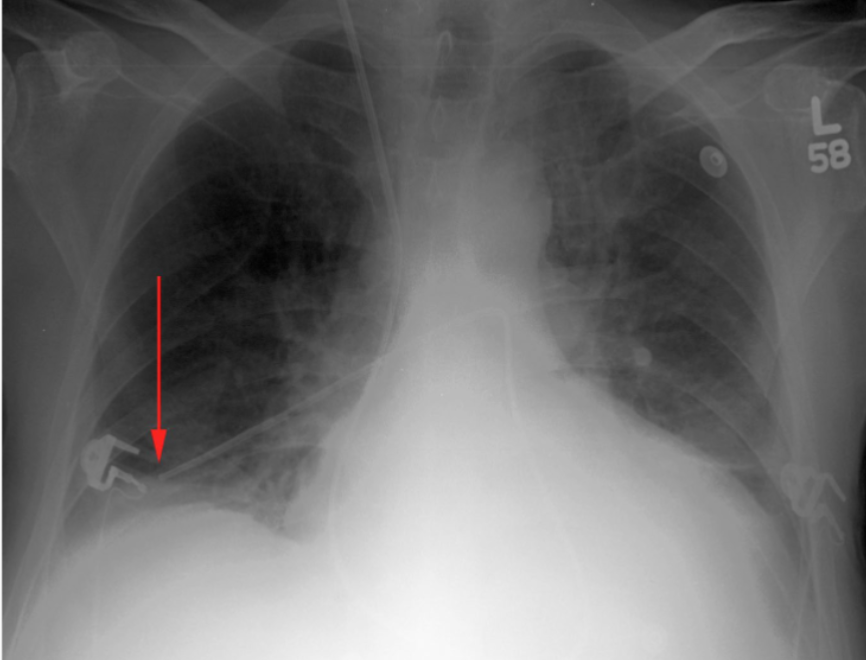

What is this patient presenting with?

Large pleural effusion (associated with “meniscus” sign)